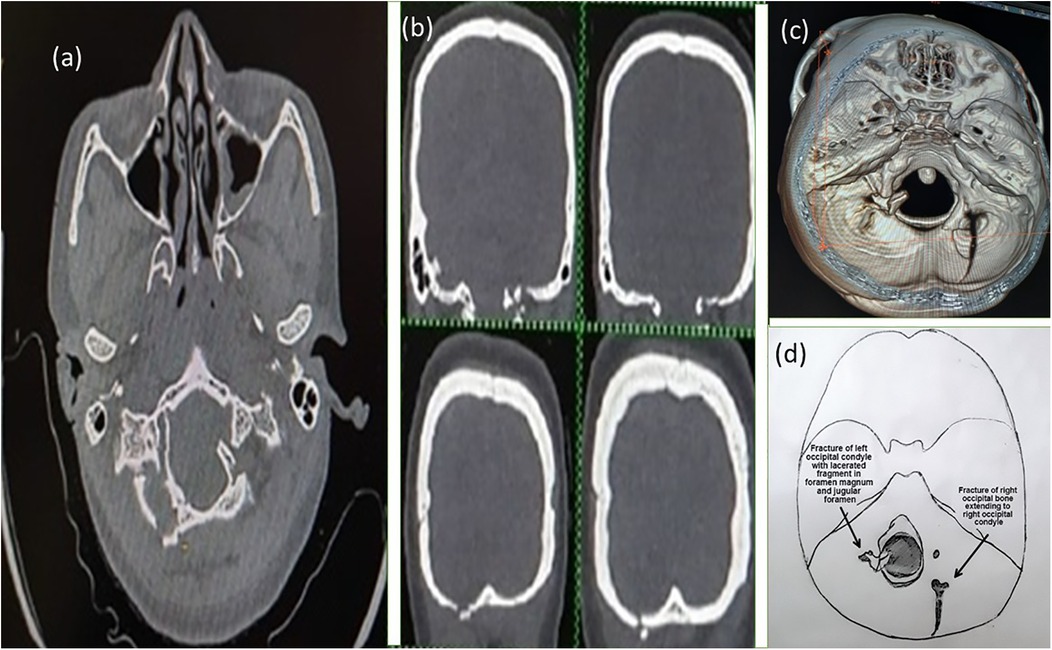

MRI scan showing a transverse section of the head, highlighting the brain structures and surrounding tissues. The image is in grayscale with varying shades indicating different tissue densities.

Figure 2. MRI of the first patient showing a lacerated fragment of the fractured occipital condyle in the foramen magnum without any neurovascular compression.